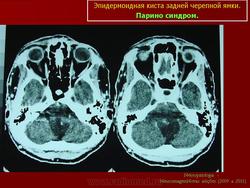

Эпидермоидные кисты задней черепной ямки - редкие новообразования. По данным Института нейрохирургии они составляют 0.5% от всех опухолей центральной нервной системы. Формирование морфологического субстрата эпидермоидных кист происходит на 3 неделе внутриутробной жизни, вследствие нарушения эмбриогенеза и смещения эпителиальной ткани в нервную трубку.

С 1985 по 2000 г.г. в НИИ нейрохирургии им. Н.Н. Бурденко обследовано и оперировано 78 больных с эпидермоидными кистами задней черепной ямки. Изучен клинический симптомокомплекс и КТ, МРТ картина эпидермоидных кист задней черепной ямки.